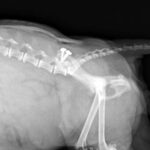

頻繁に嘔吐・下痢をするワンちゃんの精密検査依頼で内視鏡検査のご紹介がありました。内視鏡検査で上部・下部消化管を検査し、粘膜を採取し病理組織検査に出しました。結果は「胃:らせん菌感染を伴う慢性胃炎(中程度)/結腸:慢性腸炎(軽度)」とのことでした。その後かかりつけの先生のところ […]